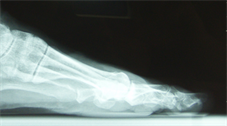

Figure 18. Patient Nr. 4. Bilateral moderate hallux valgus.

Figure 19. Patient Nr. 4. Side view left foot.

Figure 20. Patient Nr. 4. Side view right foot.

Figure 21. Patient Nr. 4. 5 years after bilateral correction. Outpatient. Immediate full weight bearing.

Figure 22. Patient Nr. 4. Side view of the left foot shows the plantarization of 2 mm.

Figure 23. Patient Nr. 4. Side view of the right foot shows the plantarization of 2 mm.